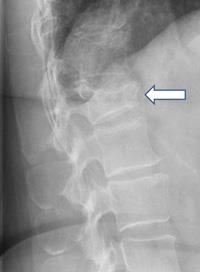

Osteoporosis X-ray - wikidoc

Spine fracture in osteoporosis, X-ray - Stock Image - C013/3034 - Science Photo Library